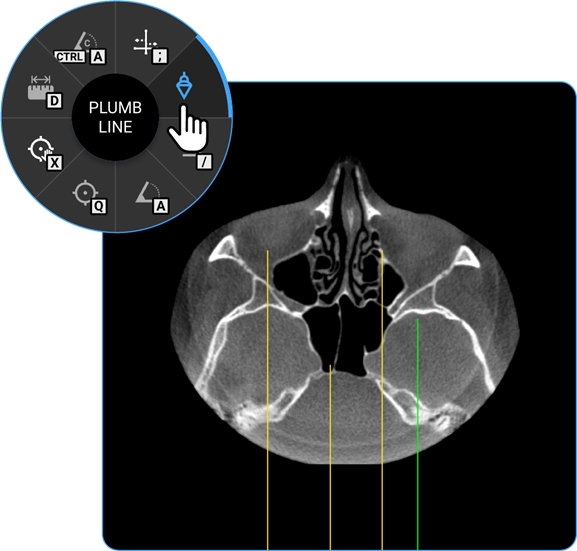

- Plumb Line: Select the Plumb Line tool to draw a vertical reference line, helpful in assessing alignment or structural deviations.